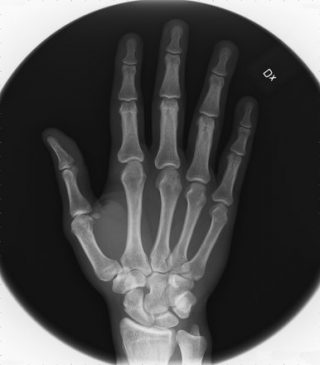

Effettivamente la mano è composta da 27 ossa da numerosi muscoli e tendini, perciò essendo così complessa e cosi tanto importante per la vita quotidiana è facile che vada incontro a traumi, lesioni ai tendinee o muscolari. Chiaramente le problematiche legate alla patologia della mano sono molto numerose, tra le più frequenti possiamo individuare le deformità che possono essere congenite, degenerative(artrosi) o infiammatorie(artrite reumatoide), patologie dei tessuti molli (come la sindrome del tunnel carpale o tenovaginaliti),

Traumi ( distacchi epifisari, fratture, lesioni tendinee, lesioni nervose).